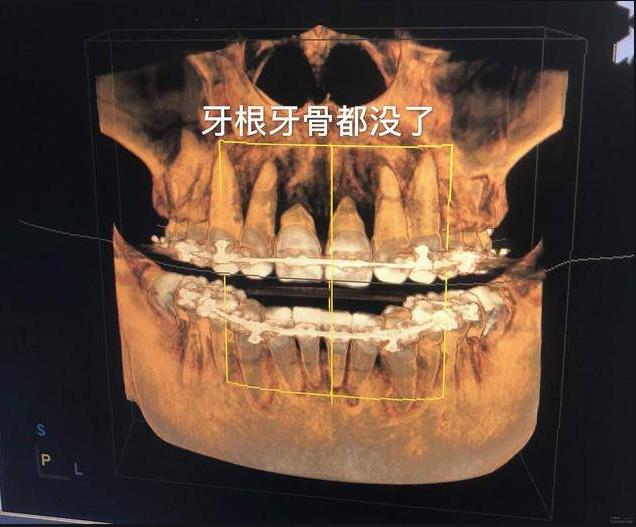

最近很多缺牙的街坊到院问医生“不是说牙齿会有根的吗?为什么我烂牙没有牙根了?”

牙根被腐蚀,引发因素很常见